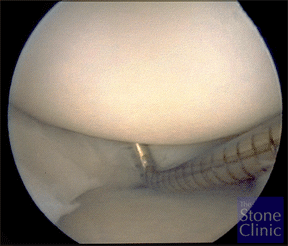

At the time of arthroscopy the meniscus was found to be chronically torn and degenerative as seen on the next picture. A meniscectomy if it had been performed at this time would leave her with essentially no meniscal rim and no protection for the joint – therefore a collagen meniscus implant was prepared as you can see in the photo on the right with a suture placed through the meniscus in order to help pull it into the knee after it was sized for the defect.

Surgery revealed a large complex, degenerative tear of the medial meniscus. The undersurface of the meniscus appeared to be sheared off and displaced into the joint. The tissue was debrided back to a stable base. The defect size was measured with a calibrated probe and noted to be 24 mm in length and 6 mm in length. The collagen meniscus implant (photo on right) was trimmed to match. The implant was soaked in venous blood for one minute and then inserted into the meniscus defect. Stitches were placed to secure the implant to the native meniscus tissue.

A follow-up second look arthroscopy with biopsy was perfomed three months later per the IRB approved FDA protocol. The implant was in place with new healed, regenerated tissue. A 2 mm defect in the radial plane was noted. The picture on the left shows an arthroscopic probe probing the regenerated meniscus tissue.